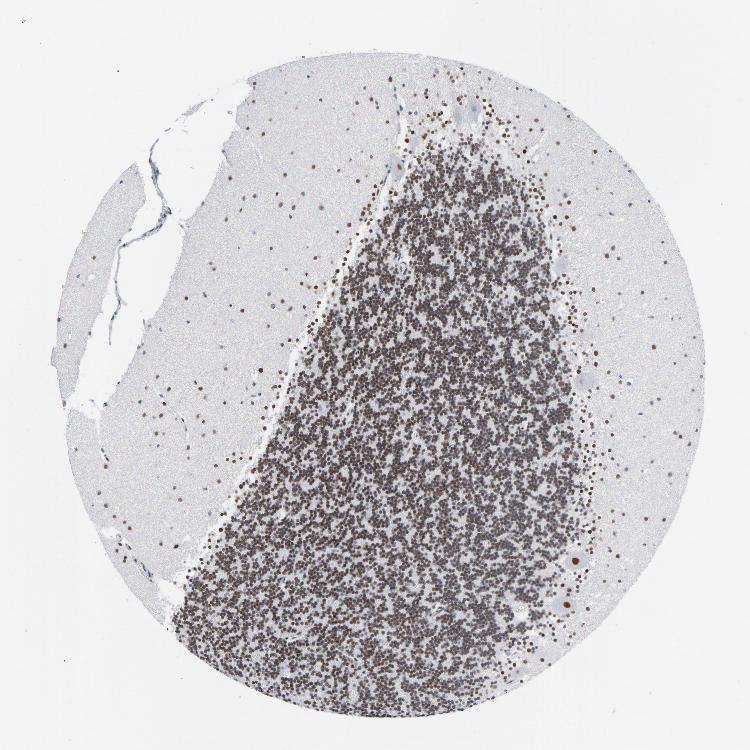

CEREBELLUM - Expression summary

CEREBELLUM - Antibody stainingi

Antibody staining in the annotated cell types in the current human tissue is reported as not detected, low, medium, or high, based on conventional immunohistochemistry profiling in selected tissues. This score is based on the combination of the staining intensity and fraction of stained cells.

Each image is clickable and will lead to virtual microscopy that enables deeper exploration of all samples and also displays staining intensity scores, fraction scores and subcellular localization as well as patient and tissue information for each sample.

Antibody HPA000427Antibody CAB004680

Purkinje cells HighHigh

Cells in granular layer HighHigh

Cells in molecular layer HighHigh